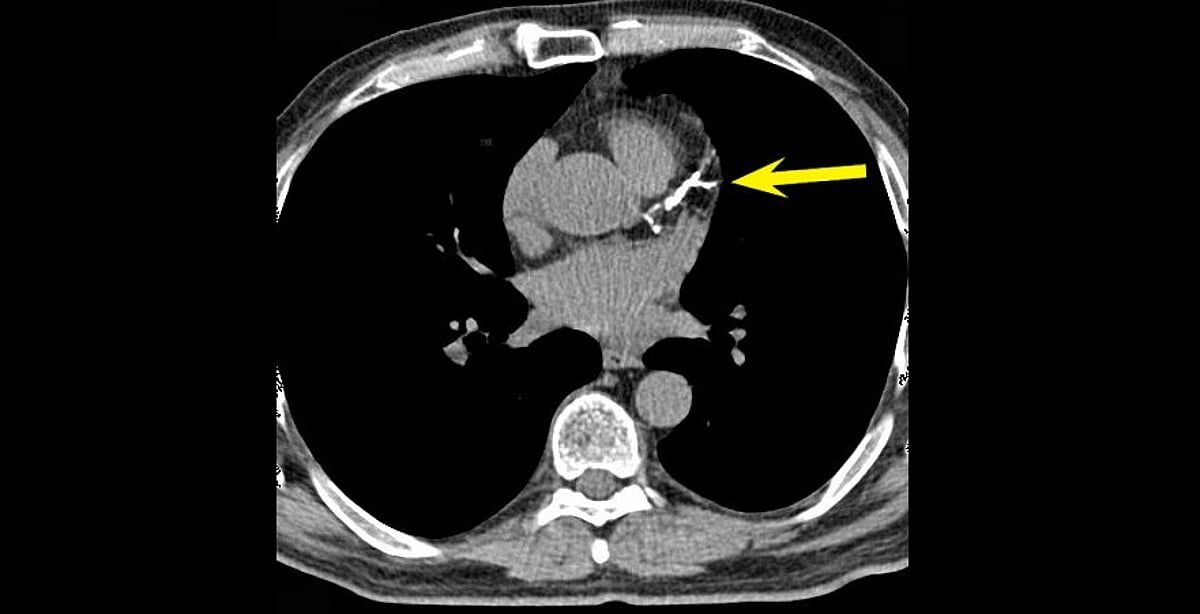

في توضيح طبي، أشار استشاري أمراض القلب الدكتور خالد ، إلى أن رقم تكلّس الشرايين (Calcium Score) غالبًا ما يرتفع تدريجيًّا مع التقدم في العمر، ووجود عوامل مثل ارتفاع ضغط الدم والسكري والتدخين، مؤكدًا أن الزيادة البسيطة لا تعني بالضرورة تدهور الحالة الصحية.

وضرب "النمر" مثالًا بأن من كان لديه رقم تكلّس 30 وأصبح 52 بعد 4 سنوات، فإن هذه الزيادة تُعد طبيعية ومتوقعة، إذ إن المعدل السنوي المقبول عادة لا يتجاوز 20 إلى 25٪.

وشدد على أهمية السيطرة على العوامل المسببة مثل الضغط، والكوليسترول، والتدخين، والوزن، حتى لا تتسارع نسبة التكلّس وتؤثر على صحة الشرايين.